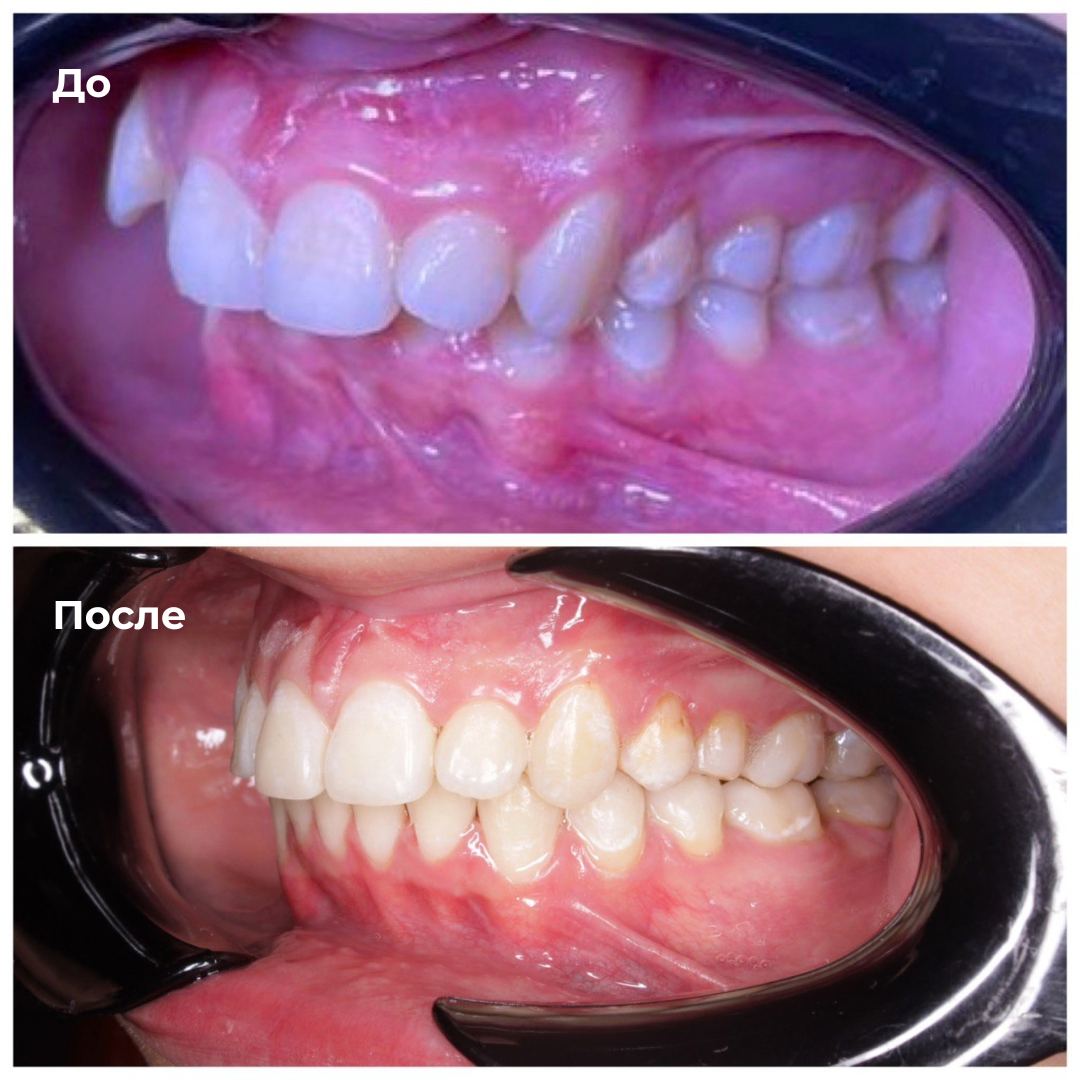

Такие результаты получают наши пациенты после лечения

Каждый случай - индивидуальный, но результат один: ровные зубы

Запишитесь на консультацию — подберём оптимальный план лечения под ваш случай.

неправильный прикус